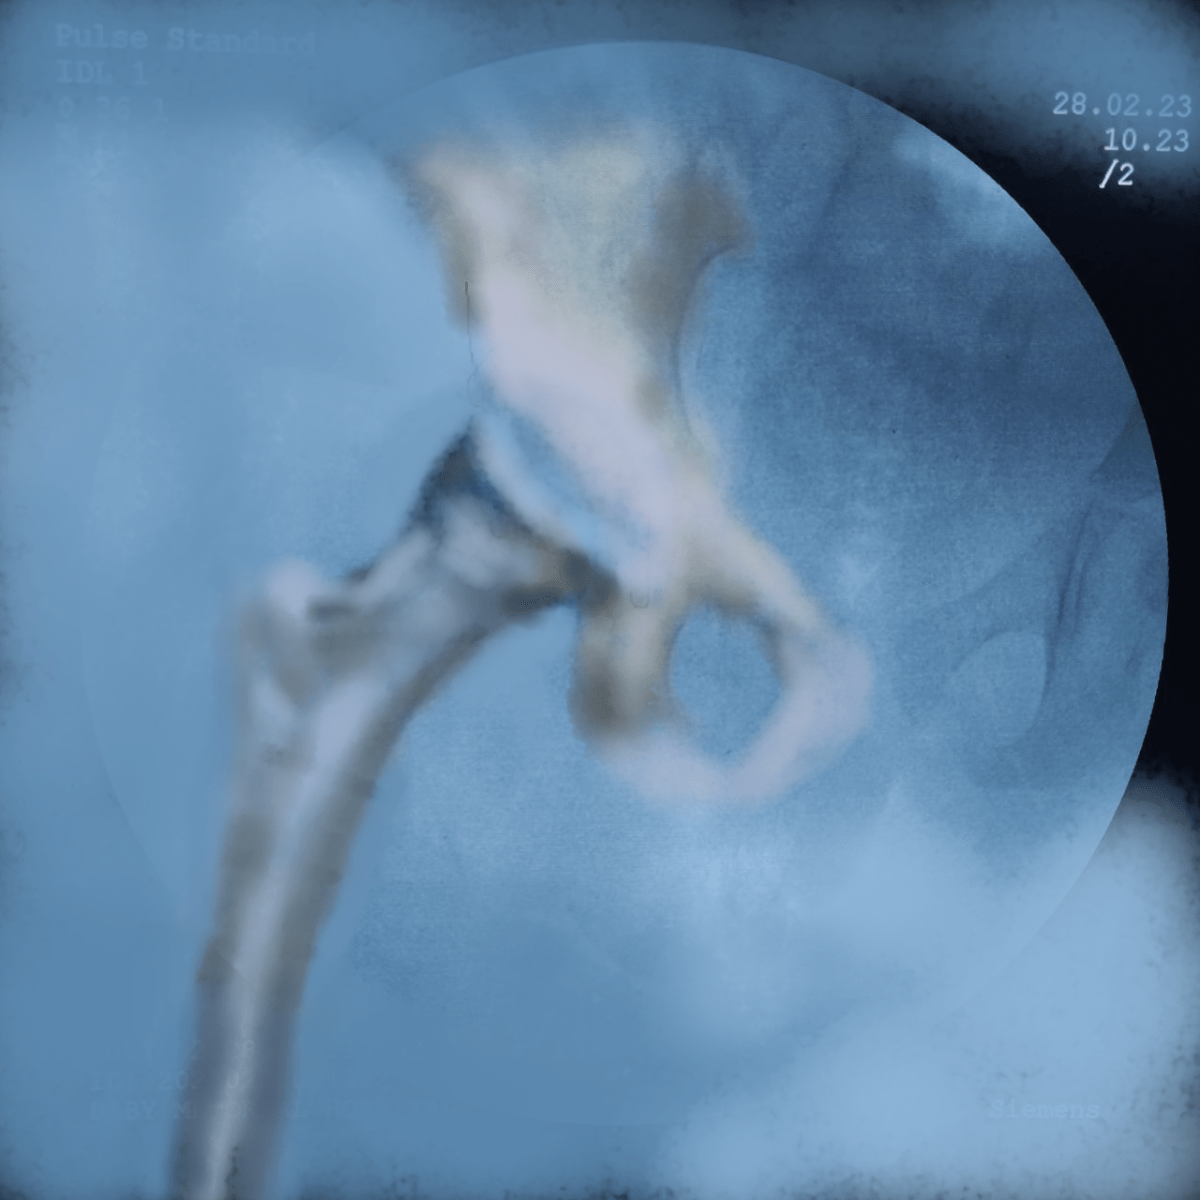

Illustrating below a case whether the Derotation osteotomy was done first and the we decided the acetabular osteotomy based on the cartilage cover on arthrogram.

The state of hip before the osteotomy. Open reduction was done elsewhere about a year ago. Persistent hip dysplasia was observed.

The Derotation osteotomy improved the coverage but we still have to decide about the acetabular procedure.

An arthrogram reveals a large cartilage cover on superolateral acetabulum. The cartilage bump is pointed to by the forceps.

The C Arm image is superimposed and an artist’s impression is drawn showing what the cartilage would look like in 3D. This offers an excellent teaching tool and a 3D orientation for young surgeons and pediatric orthopedic trainees to decide whether an acetabular osteotomy is needed

The surgeon would then discuss with parents and opt to continue an acetabular procedure of take a staged approach